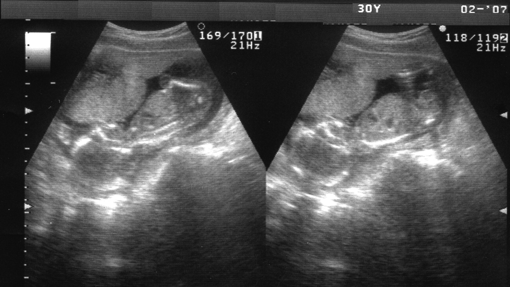

Un útero artificial

Científicos estadounidenses desarrollaron un dispositivo artificial que emula las condiciones en el interior del útero materno y lograron mantener con vida durante cuatro semanas a fetos de cordero «extremadamente prematuros». El estudio “ An extra-uterine system to physiologically support the extreme premature lamb ”, publicado en «Nature Communications» mostraba cómo los investigadores del Hospital Infantil de Filadelfia han creado un «ambiente fluido» artificial a partir de una bolsa de polietileno que incorpora un circuito de oxígeno, un sistema con el que han logrado que animales mantengan una circulación sanguínea y de gases estable. Para probar ese sistema extrauterino se han utilizado corderos con una edad biológica equivalente a un neonato humano en las semanas 23 o 24 de gestación. « Nuestro sistema podría prevenir la severa morbilidad que se produce en niños extremadamente prematuros. Ofrece una tecnología médica que no estaba disponible hasta ahora », sostuvo Alan Flake, autor principal del trabajo. «Esta investigación no aspira a reemplazar el útero durante la primera parte del embarazo, sino que intenta desarrollar nuevos modos de tratar a los bebés prematuros», señaló el profesor de la Universidad de Edimburgo (Reino Unido) Colin Duncan.